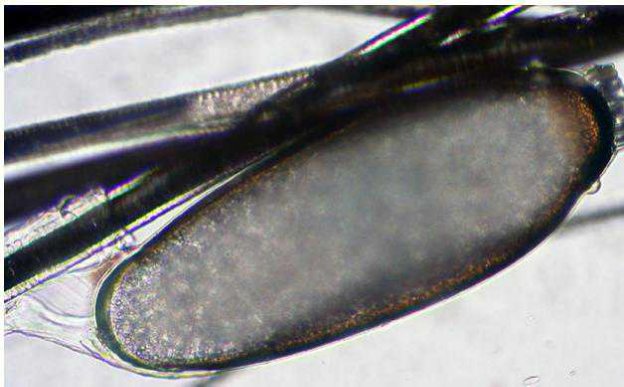

Con l’esame tricoscopico è possibile infine evidenziare la presenza di Demodex, uova di Cheyletiella e adulti e uova di pidocchi.

Figura 4 - Esame tricoscopico di un cane con alopecia multifocale: numerousi adulti di Demodex canis.

Figura 5 - Esame tricoscopico di un gatto con alopecia rarefazione del mantello: uovo di pidocchio (lendine) adesa al fusto pilifero.